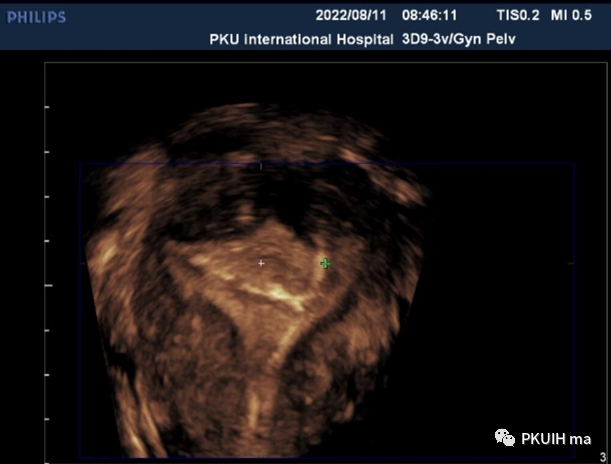

上面是一个二维图像显示热指数是0.6,机械指数是0.9,颜色显示正常的白色。咱们再来看下面的三维图像

同样孕周大小胎儿做了三维图像显示热指数和机械指数分别是0.4、0.8并没有大于二维超声图像。同样下图三维超声热指数和机械指数是0.3和1.1,热指数也是很低的